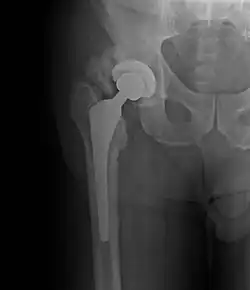

| Heterotopic ossification around the hip joint in a patient who has undergone hip arthroplasty |

Heterotopic ossification (HO) is the process by which bone tissue forms outside of the skeleton in muscles and soft tissue.[1]

Heterotopic ossification of varying severity can be caused by surgery or trauma to the hips and legs. About every third patient who has total hip arthroplasty (joint replacement) or a severe fracture of the long bones of the lower leg will develop heterotopic ossification, but is uncommonly symptomatic. Between 50% and 90% of patients who developed heterotopic ossification following a previous hip arthroplasty will develop additional heterotopic ossification.